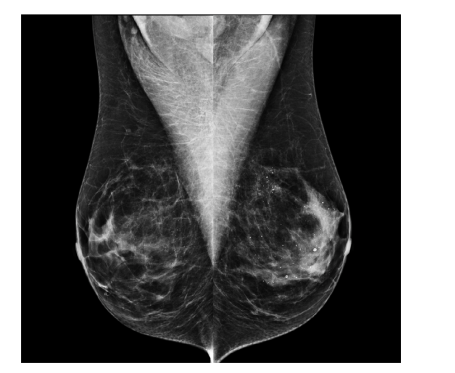

Fig. 14. Example of negative control that was classified as positive by the AGN4Varchitecture. Note the asymmetry between the left and right breast.

图14. 一个被AGN4V架构分类为阳性的阴性对照示例。请注意左侧和右侧乳房之间的不对称性。